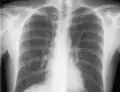

Neumotórax

La incidencia de neumotórax es mayor con el cateterismo de la vena subclavia debido a su proximidad anatómica al ápice del pulmón. En el caso de la cateterización de la vena yugular interna, el riesgo de neumotórax se minimiza mediante el uso de guía ecográfica. Para los médicos experimentados, la incidencia de neumotórax es de aproximadamente 1.5 a 3.1%. El Instituto Nacional de Salud y Excelencia Clínica (Reino Unido) y otras organizaciones médicas recomiendan el uso rutinario de la ecografía para minimizar las complicaciones.[5]

Si se sospecha un neumotórax, se debe obtener una radiografía de tórax en posición vertical del paciente. Se prefiere una radiografía de tórax en posición vertical porque el aire libre migrará al vértice del pulmón, donde se visualiza fácilmente. Por supuesto, esto no siempre es posible, especialmente en pacientes críticamente enfermos en la unidad de cuidados intensivos. Las radiografías obtenidas en decúbito supino no detectan entre el 25 y el 50% de los neumotórax.[6] Sin embargo, la ecografía puede usarse como método de detección en personas demasiado enfermas para obtener imágenes en posición vertical.[3]